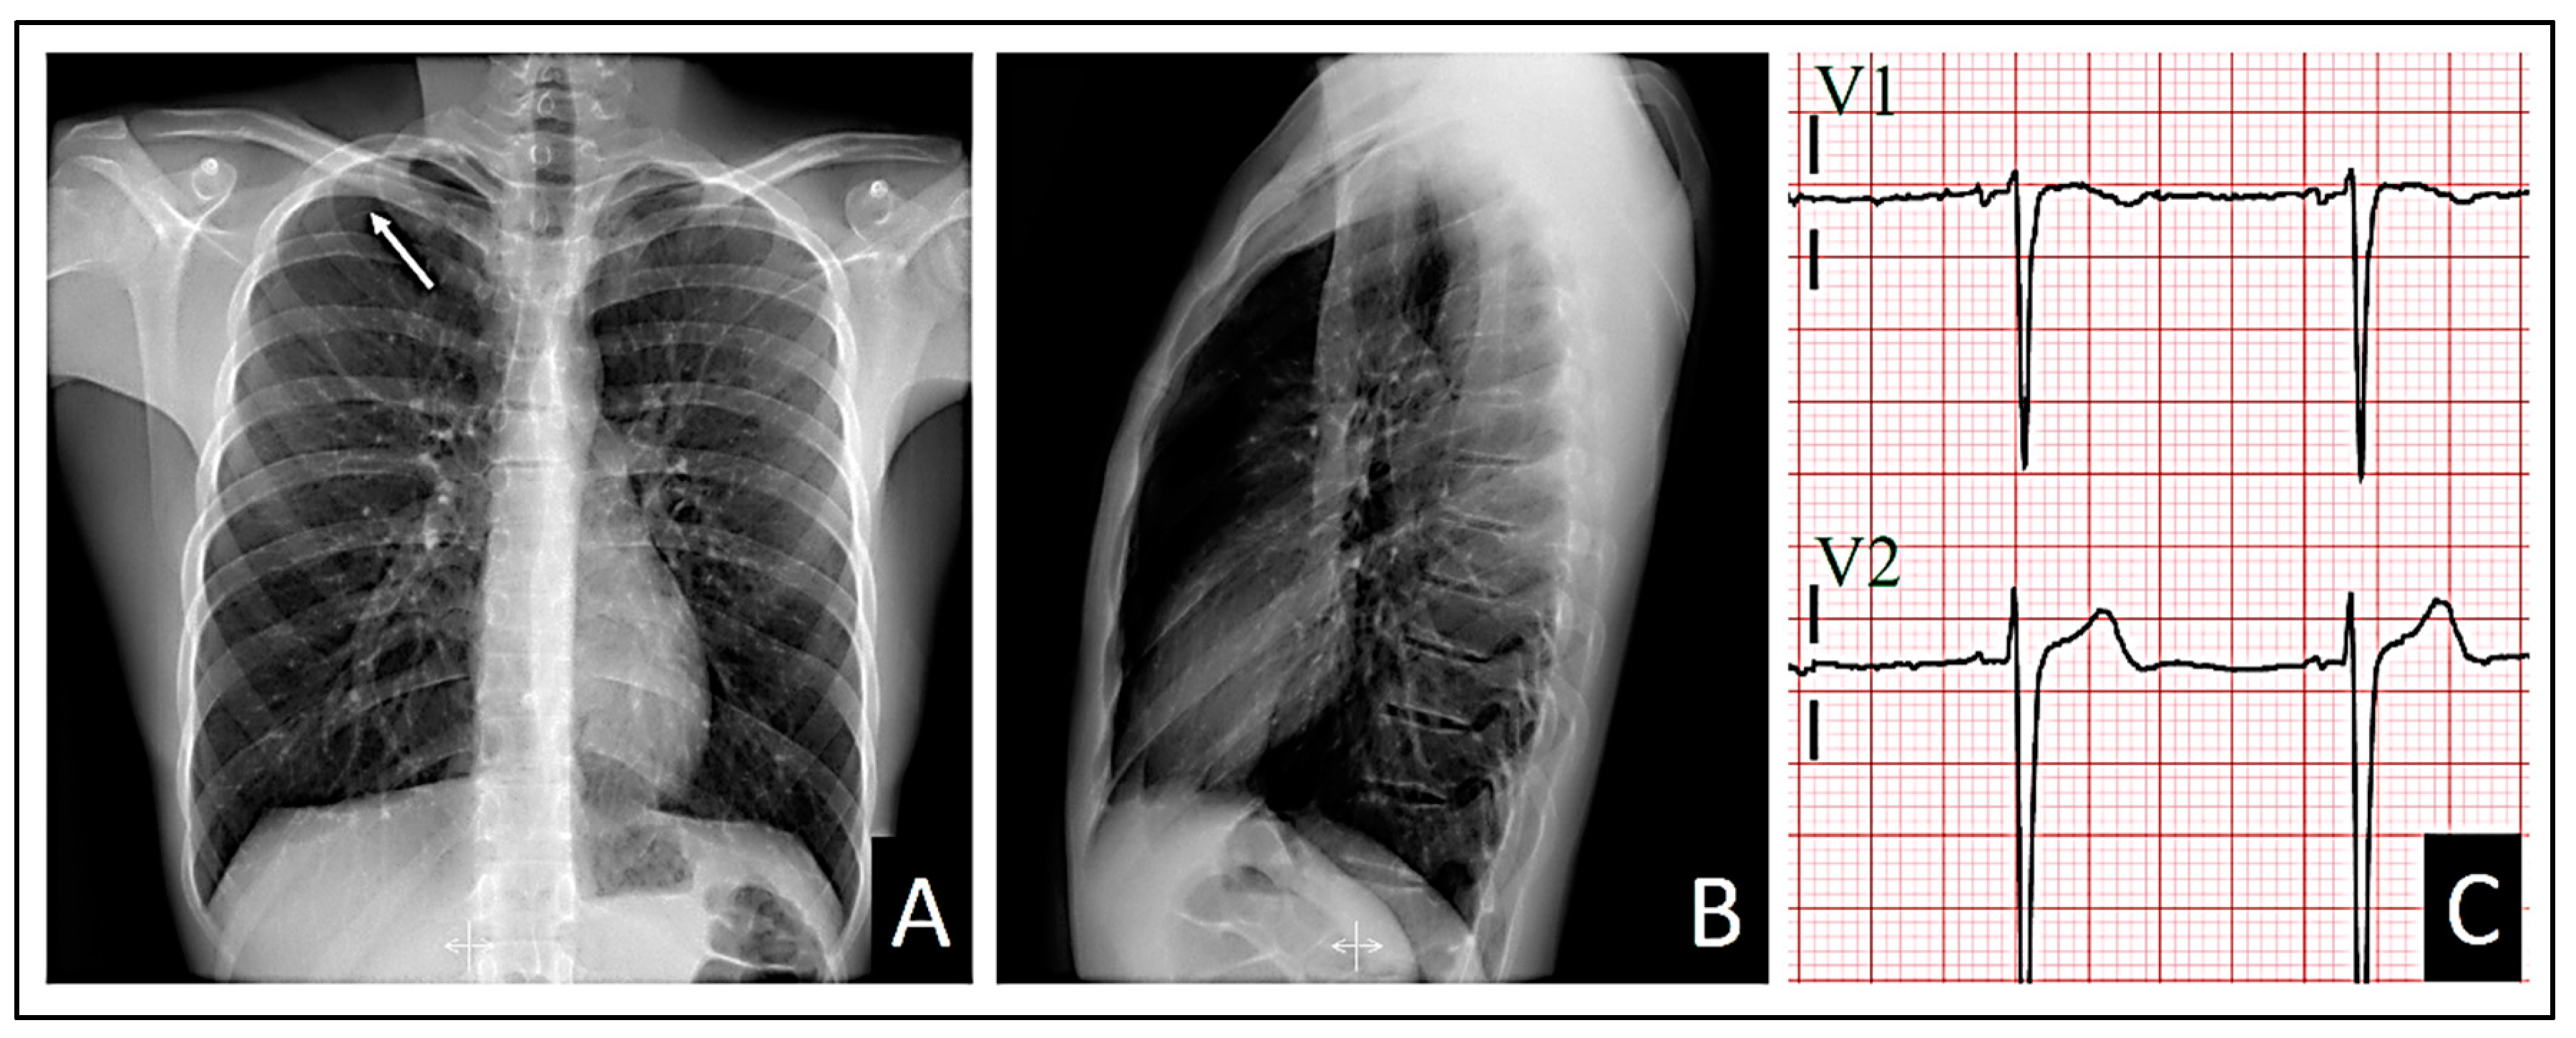

The standard 12-lead electrocardiogram, performed with precordial electrodes in their typical positions (V1 and V2 is in the fourth intercostal space), showed a type 2 Brugada pattern in V2 and a type 3 pattern in V1, with a β angle [10,11,12] measuring over 58º (Figure 2). We also confirmed the QRS axis in the frontal plane to be 85º-90º.

When we displaced two intercostal spaces below their normal positions, the observed patterns vanished (Figure 3).

When we assessed the right precordial leads using V1 and V2 two intercostal spaces above the normal position, that is, at the level of the second intercostal space, the pattern in V2 shifted to a type 3 pattern, while the pattern in V1 persisted, albeit with a less pronounced morphology upon visual inspection (Figure 4). The right precordial leads were evaluated in search of patterns at those levels. However, no pathological changes in repolarization were evident from V3R to V6R.

The left leads with V1 and V2 at the third intercostal space showed an intermediate morphology between the morphologies observed at the second intercostal space and the normal position (Figure 5).

Both the chest X-ray and electrocardiogram were repeated at 48 hours, revealing an improvement in the pneumothorax with a halving of the pleural space volume, alongside the disappearance of Brugada patterns displaying appropriate morphology for identification. In lead V1, a tendency toward β angle formation persists, while in V2, a 1 mm elevation of the J point is evident with T-wave morphology tending to notch at its center. Nonetheless, no curves exhibit morphology of sufficient quality to suggest a pattern visually.

Figure 6. At 48 hours. A: Posteroanterior chest X-ray demonstrating improvement of the pneumothorax. B: Lateral chest X-ray still demonstrating absence of cardiac compression due to the patient’s thoracic morphology. C: Loss of Brugada patterns with the required quality for consideration.